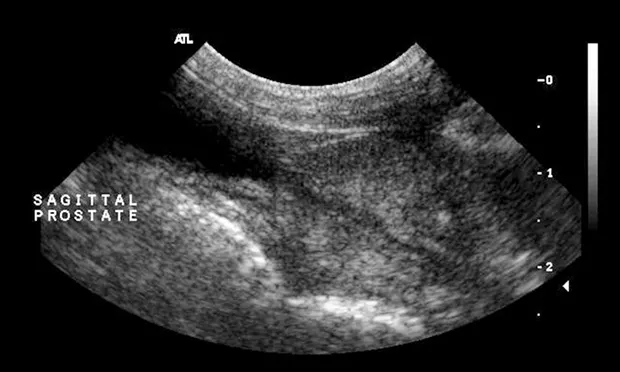

Abdominal ultrasonography—including both inguinal canals to the extent that was possible—disclosed no abnormalities, including presence of an abdominal testis. The prostate appeared enlarged and hyperechoic—typical of a mature male (Figures 1 and 2).

Figure 2. Sagittal image of a normal prostate in an intact dog; note the increased echogenicity of the prostatic parenchyma